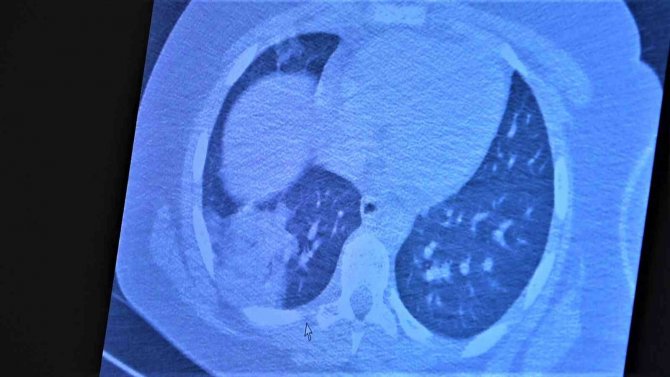

Çocukların akciğer tomografilerini inceleyen Özkaya, "11 yaşında kovid pozitif bir öğrencimiz, yüksek ateş ve nefes darlığı ile bize geldi. Ciddi akciğer tutulumu var. Geçen yıl "bu çocuklar hastalıktan etkilenmiyor" diyorduk. Bu çocukta görüyorsunuz buzlu camlar ve konsolidasyon alanlarla seyrediyor. Geçen yıl bu şekilde çok çocuk görmüyorduk. Önümüzdeki aylarda bu şekilde devam ederse çocuklarımızı kaybetmeye bile başlayabiliriz. 14 yaşında pozitif olan bir diğer çocuğumuz ise aşı randevusu almış ama aşısını olmadan ateş ve öksürükle başvurdu. Halen şanslıyız. Çocuklar çok hızlı tedaviye yanıt veriyor. Düzeldi. Çekilen tomografisinde ise bilaterel yaygın tutulumları vardı. Bu ise 24 yaşında genç hastanın akciğer tomografisi. Bu kişide yaygın akciğer tutulumları görüldü. Bunu da tedavi ettik. Önümüzdeki aylarda ne getirecek ne götürecek beraber göreceğiz. Özellikle havaların soğumasıyla kapalı ortamlarda geçilen zamanın ve kalabalıkların etkisiyle vaka sayılarının önümüzdeki günlerde artacağını biliyoruz. Şu an gerçekten hastalık gençlerde 30 -40 yaş altı gençlerde görülmeye başladı. Poliklinik şartlarında olanların büyük bir kısmı 30 yaş altı hastalar. Servislerde yatanlarda orta yaş ve altı nüfus. Yoğun bakımda yatanların büyük bir kısmı ise aşısız erişkin insanlardan oluşuyor" diye konuştu.